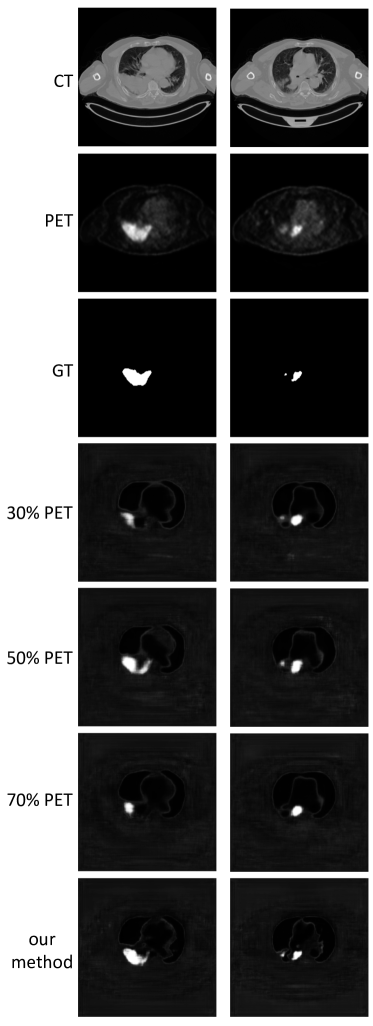

We extracted the feature fusion maps produced by the co-learning unit (see Section II-D) to examine the fusion ratios that were produced for an image with a tumor inside the lung field. This experiment was undertaken to confirm whether the fusion ratios that were automatically derived matched the well-established expectations. Further analysis on a heterogeneous tumor was performed for the Supplementary Materials (see Section S3). We also visually compared the results derived using our co-learning CNN’s spatially varying fusion to the results derived from using different uniform fusion ratios with the FS architecture. We used uniform fusion ratios that included mainly anatomical information (30% PET with 70% CT), equal information (50% PET and CT), and mainly functional information (70% PET with 30% CT).

Fig. 8 is a visual comparison of the results obtained by our co-learning CNN to the results obtained with uniform fusion; a larger version is included as Fig. S6 in the Supplementary Materials. The figure shows that our CNN has visually consistent tumor detection across both studies. In contrast, the figure visually shows that a uniform fusion ratio may not be optimal for different studies; equal (50%) PET and CT is the better ratio for detecting the tumor in the study in the left column, while reduced (30%) PET is the better ratio for the detecting the tumors in study in the right column. The uniform fusion results were sensitive to the fusion ratio and the specific PET-CT images being processed, and across different studies produced probability maps that either missed tumors or overestimated the tumor area.